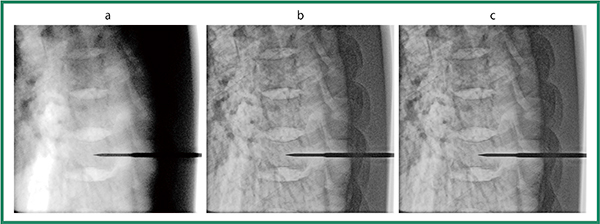

図4 画像処理の効果

a:処理なし 8.4mA b:ダイナミック処理後 8.4mA c:ダイナミック処理+ノイズ抑制処理後 4.2mA